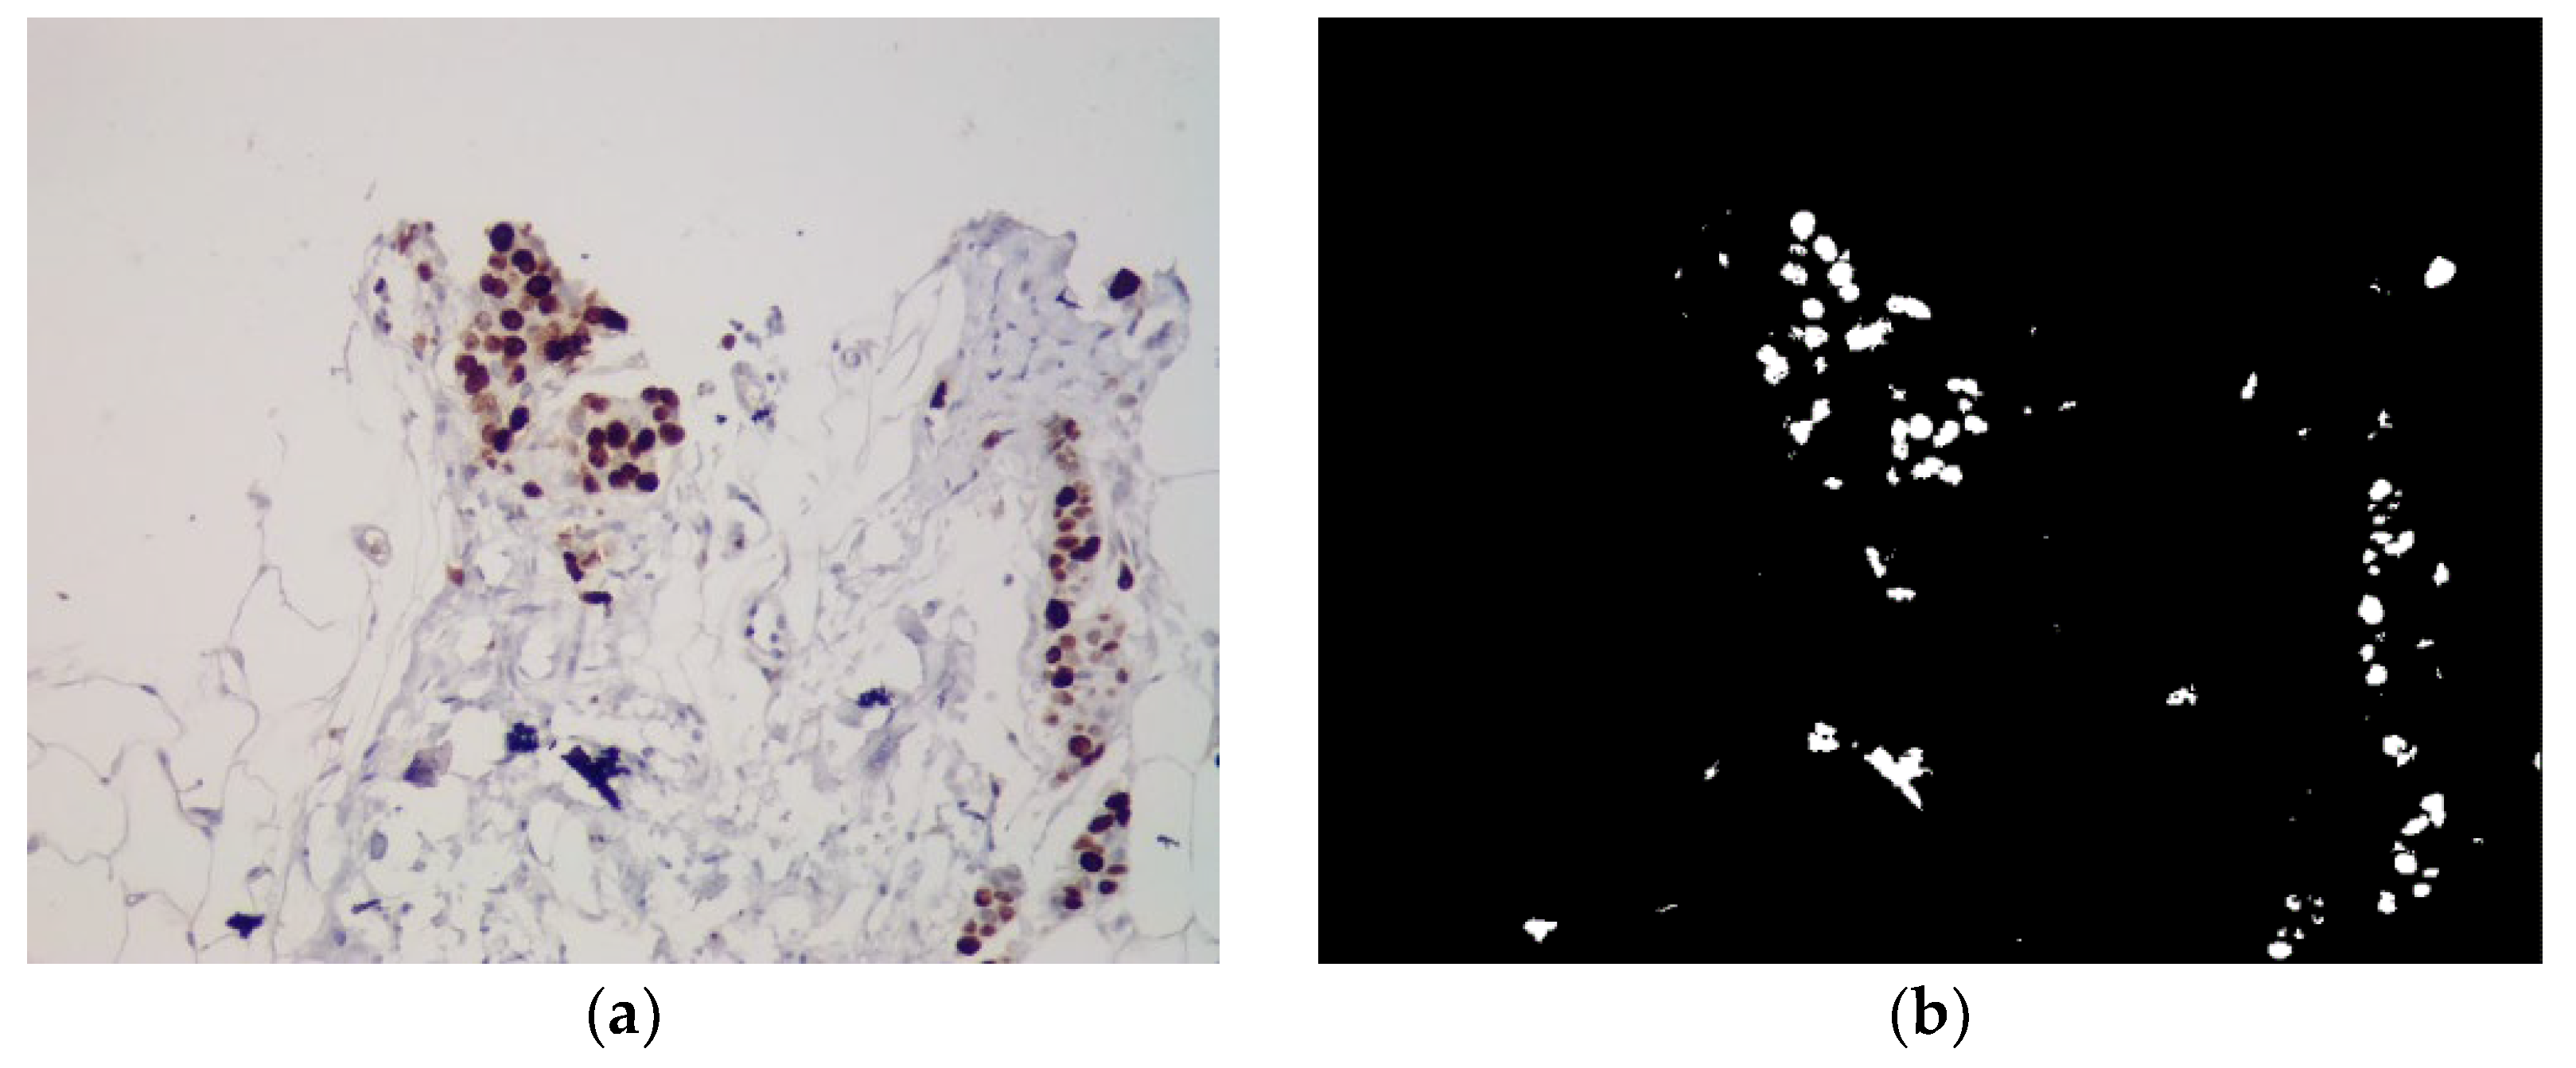

Machine learning requires the availability of both software tools for the implementation of a specific task and the availability of a prepared dataset. Dataset preparation depends on the task at hand. For example, for the task of classification, the sample is usually divided into training and test in the form of separate directories in the file system. For the task of implementing automatic segmentation of images based on U-net networks, it is necessary to take into account such an additional factor as “images - masks”. Currently, there are a large number of datasets in open access, but their files are formed in a different manner, which implies the need for their additional processing. An example of immunohistochemical images for automatic segmentation is shown in Figure 2.

Figure 2. Example of immunohistochemical images. (a) Original; (b) Mask.